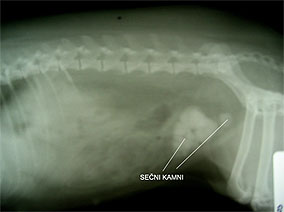

Fotografije prikazujejo primer sečnih kamnov v mehurju izjemne velikosti pri 9 let stari psički pasme nemški pritlikavi špic. Lastnik je psico pripeljal na pregled, ker je opazil oteženo in pogosto uriniranje (dysuria, polakisuria). Psica pred obiskom ni nikoli imela težav s sečili. S paplpacijo abdomna smo ugotovili v področju mehurja rezistence in posumili na sečne kamne, ki smo jih z rentgeniziranjem tudi potrdili. Psico smo pred kirurškim posegom temeljito preiskali in ugotovili še holosistolični šum na srcu, ki je simptom okvarjene mitralne srčne zaklopke. Z rentgeniziranjem prsnega koša nismo ugotovili pljučnega edema in smo se zaradi tega skupaj z lastnikom dogovorili za takojšnjo operacijo. Po operaciji smo psici pustili urinski kateter v mehurju še tri dni, predpisali antibiotično terapijo in ustrezno dijeto za preprečevanje nastajanja sečnih kamnov.

Rentgenski posnetek abdomna.

Jasno vidni kamni v sečnem mehurju.